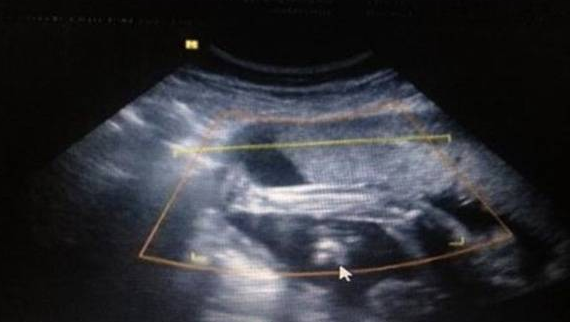

孕囊形状看性别超准方法分享,已生男孩的孕囊图片参考

对于准妈妈来说,在确定怀孕以后,很想知道胎儿性别是男孩还是女孩,会通过生男生女的特征判断胎儿性别,最近在网络上有宝妈分享已生男孩孕囊图片,据说孕囊形状呈长条形或茄子形,可能生男孩,如果孕囊形状呈圆形或椭圆形,那么生女孩的几率较大,很多准妈妈都想试一试,但是仍然有孕妇不知道哪种孕囊属于茄子型,下面详细为大家介绍生儿子孕囊形状图,一起来看看吧。已生男孩阴超孕囊参考图片B超是孕初期重要检查项目,在怀孕1